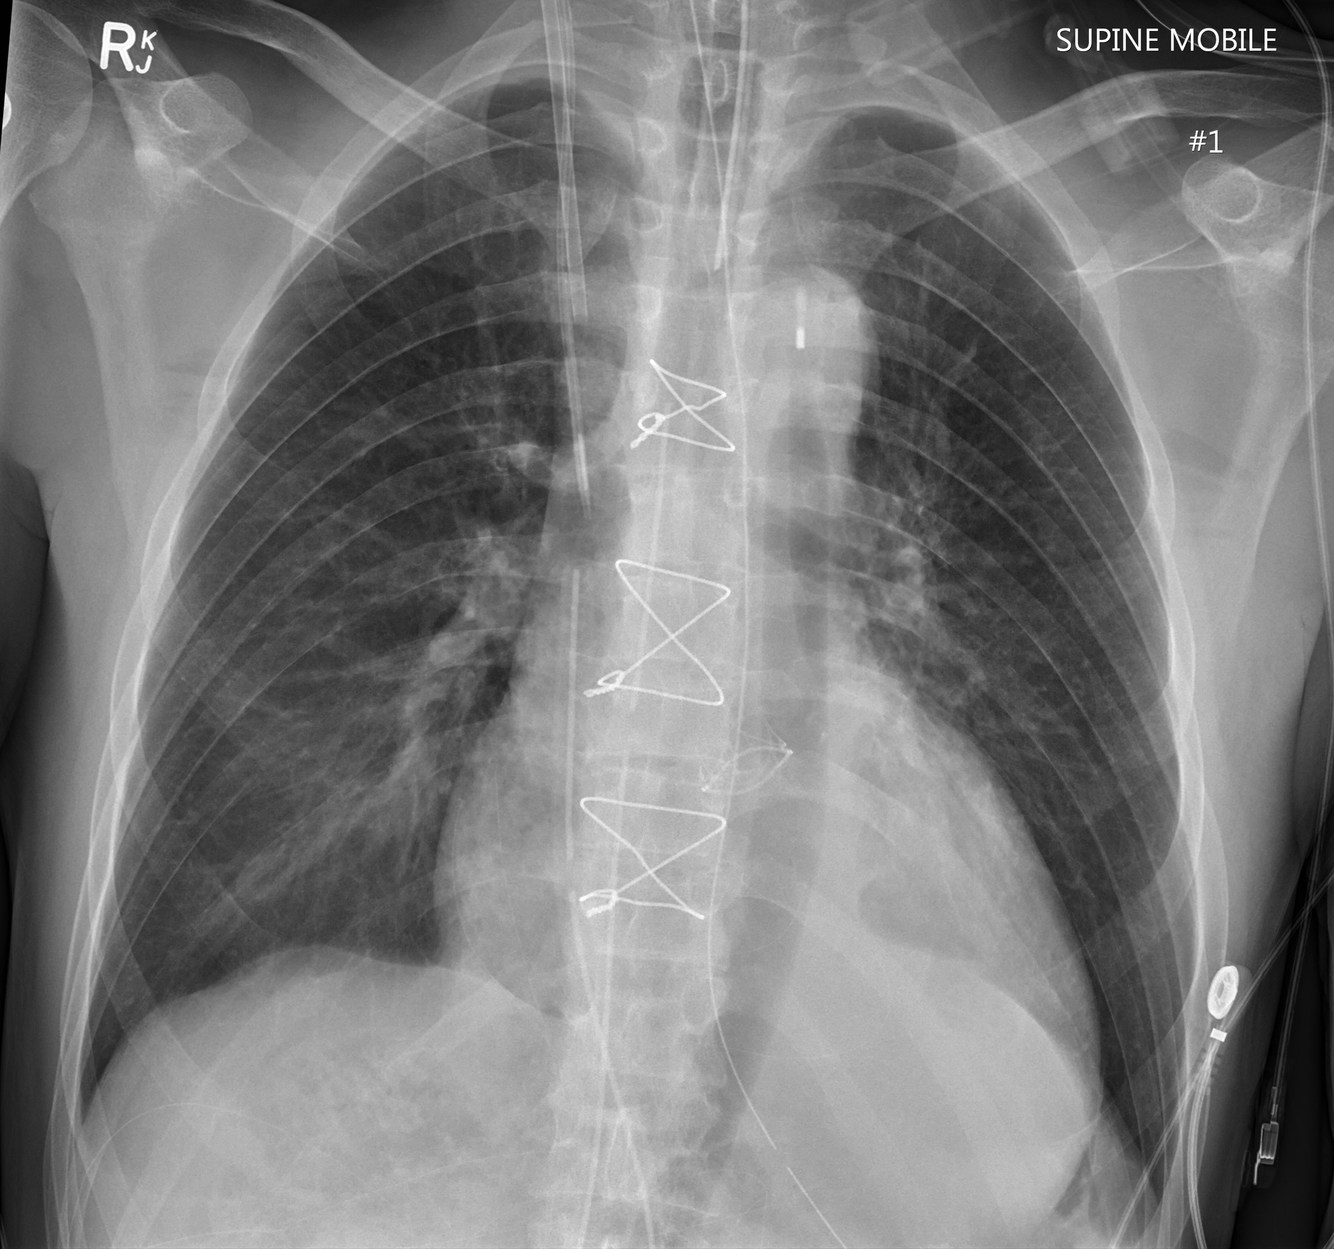

Where should the tip of an Intraaortic Balloon Pump (IABP) be?

Intraaortic Balloon Pump (IABP)

Tip should be located just distal to the takeoff of the left subclavian artery (LSA) and be 2–4 cm below aortic knob. Inflation may be seen during diastole.

The balloon should be located in the proximal descending aorta, just below the origin of the left subclavian artery. On a chest radiograph, it should be at the level of the AP window. This ideally results in the balloon terminating just above the splanchnic vessels 3.

Case courtesy of Assoc Prof Craig Hacking, Radiopaedia.org, rID: 66474